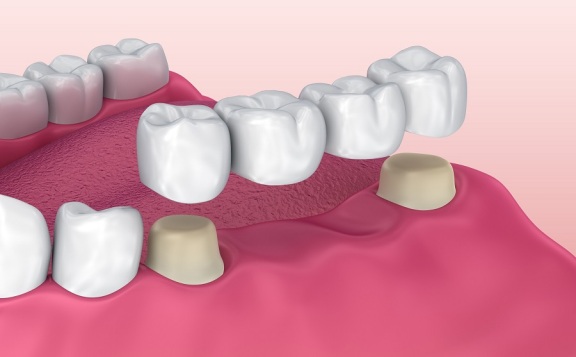

درمان ایمپلنت، که روشی برای جایگزینی دندانهای از دست رفته می باشد، یکی از بزرگترین لطفهای علم دندانپزشکی به بشریت است. تا پیش از ایمپلنت، روشهای دیگری نظیر بریج، اف ار سی، فیلیپر و پروتز متحرک وظیفه پر کردن جای خالی دندانهای از دست رفته را داشت. این روشها مشابه دندان واقعی برای بیمار کار نمی کنند و جای خالی دندان واقعی را مثل روز اول پر نخواهند کرد. اما امروزه با پیشرفت علم دندانپزشکی، ایمپلنت دندان به افراد کمک کرده تا در صورت از دست دادن دندانهای خود به راحتی سراغ درمان و جایگزین کردن آنها بروند.

درمان ایمپلنت به شما این اجازه را میدهد که پس از تکمیل دوره درمان، دندانی طبیعی داشته باشید و بدون نگرانی مثل سابق به خوردن و جویدن ادامه دهید. این روش نسبت به روشهای قدیمی مانند بریج هم میزان موفقیت بیشتر و هم عوارض کمتری برای لثهها و دندانهای مجاور دارد.

گاهی اوقات برای 3تا4 دندان که در مجاورت هم از دست رفته اند فقط به دو ایمپلنت نیاز است ولی از 4 روکش استفاده میگردد در این شرایط هزینه بیمار معادل دو ایمپلنت و دو روکش است درواقع هزینه بیمار از آنچه تصور دارد و خودشان محاسبه میکنند کمتر خواهد بود(مشابه عکس پائین)